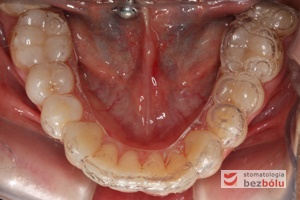

- Pobranie wycisków masą alginatową.

- Odlanie modelu protetycznego diagnostycznego.